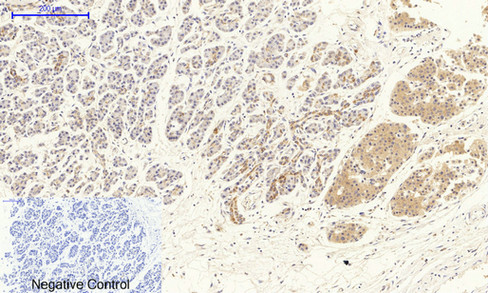

Immunohistochemical analysis of paraffin-embedded Human stomach cancer tissue using VEGFR2 Polyclonal Antibody.Negative control was used by secondary antibody only.